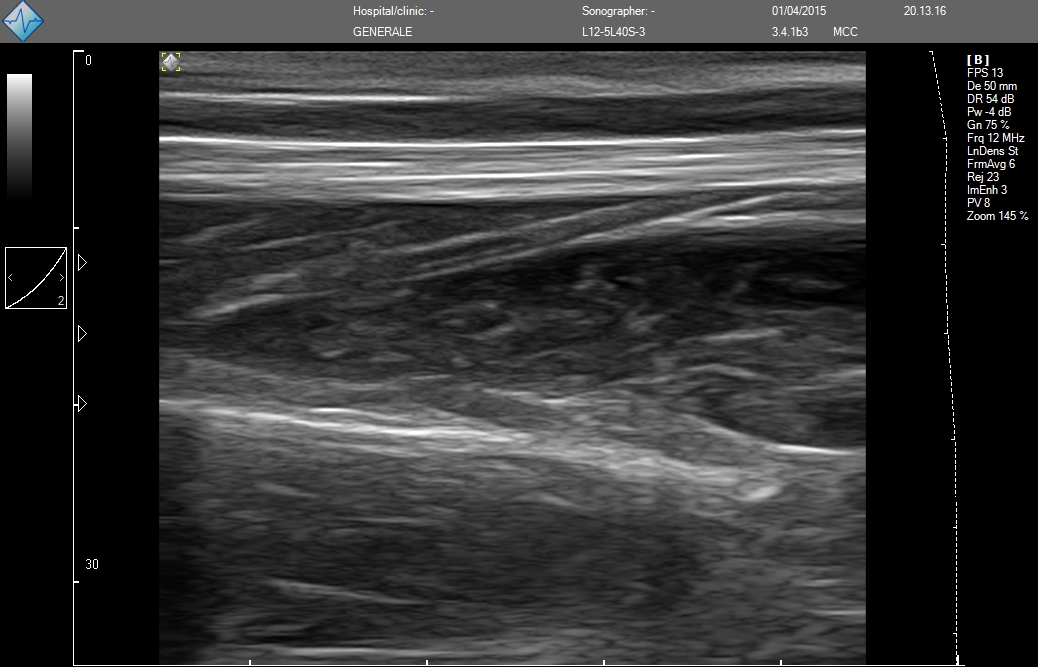

E-FAST (расширенный-FAST) дополнительно обследует переднюю и боковую плевральную полость (торакальная проекция) для оценки наличия пневмоторакса или плеврального выпота, предположительно гемоторакса у пациентов с травмой.

E-FAST имеет высокую чувствительность и специфичность (особенно в условиях гипотонии), может быть выполнен быстро, неинвазивно, без лучевой нагрузки, и может проводиться повторно. Благодаря таким преимуществам ультразвук по существу заменил диагностический перитонеальный лаваж (ДПЛ) при обследовании пациентов с травмой.

- MicrUs Pro-L40S (линейный, 5-12 МГц, 40 мм)

MicrUs Pro-L40N (линейный, 5-12 МГц, 40 мм, производительная версия)